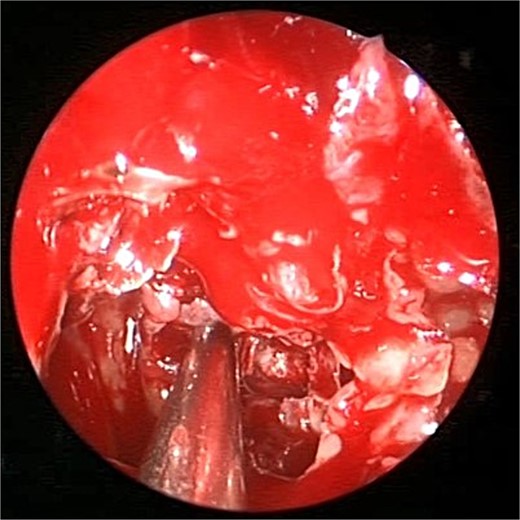

Intra-operative (A and B) endoscopic sphenoidotomy showing fungal debris, with post-operative examination (C) showing clean wide sphenoid sinus free from fungal debris.

Intra-operative (a, b, and c) endoscopic sphenoidotomy showing mud and mucin, with post-operative examination (d) of right optico-carotid recess showing wide and clean sphenoid sinus.